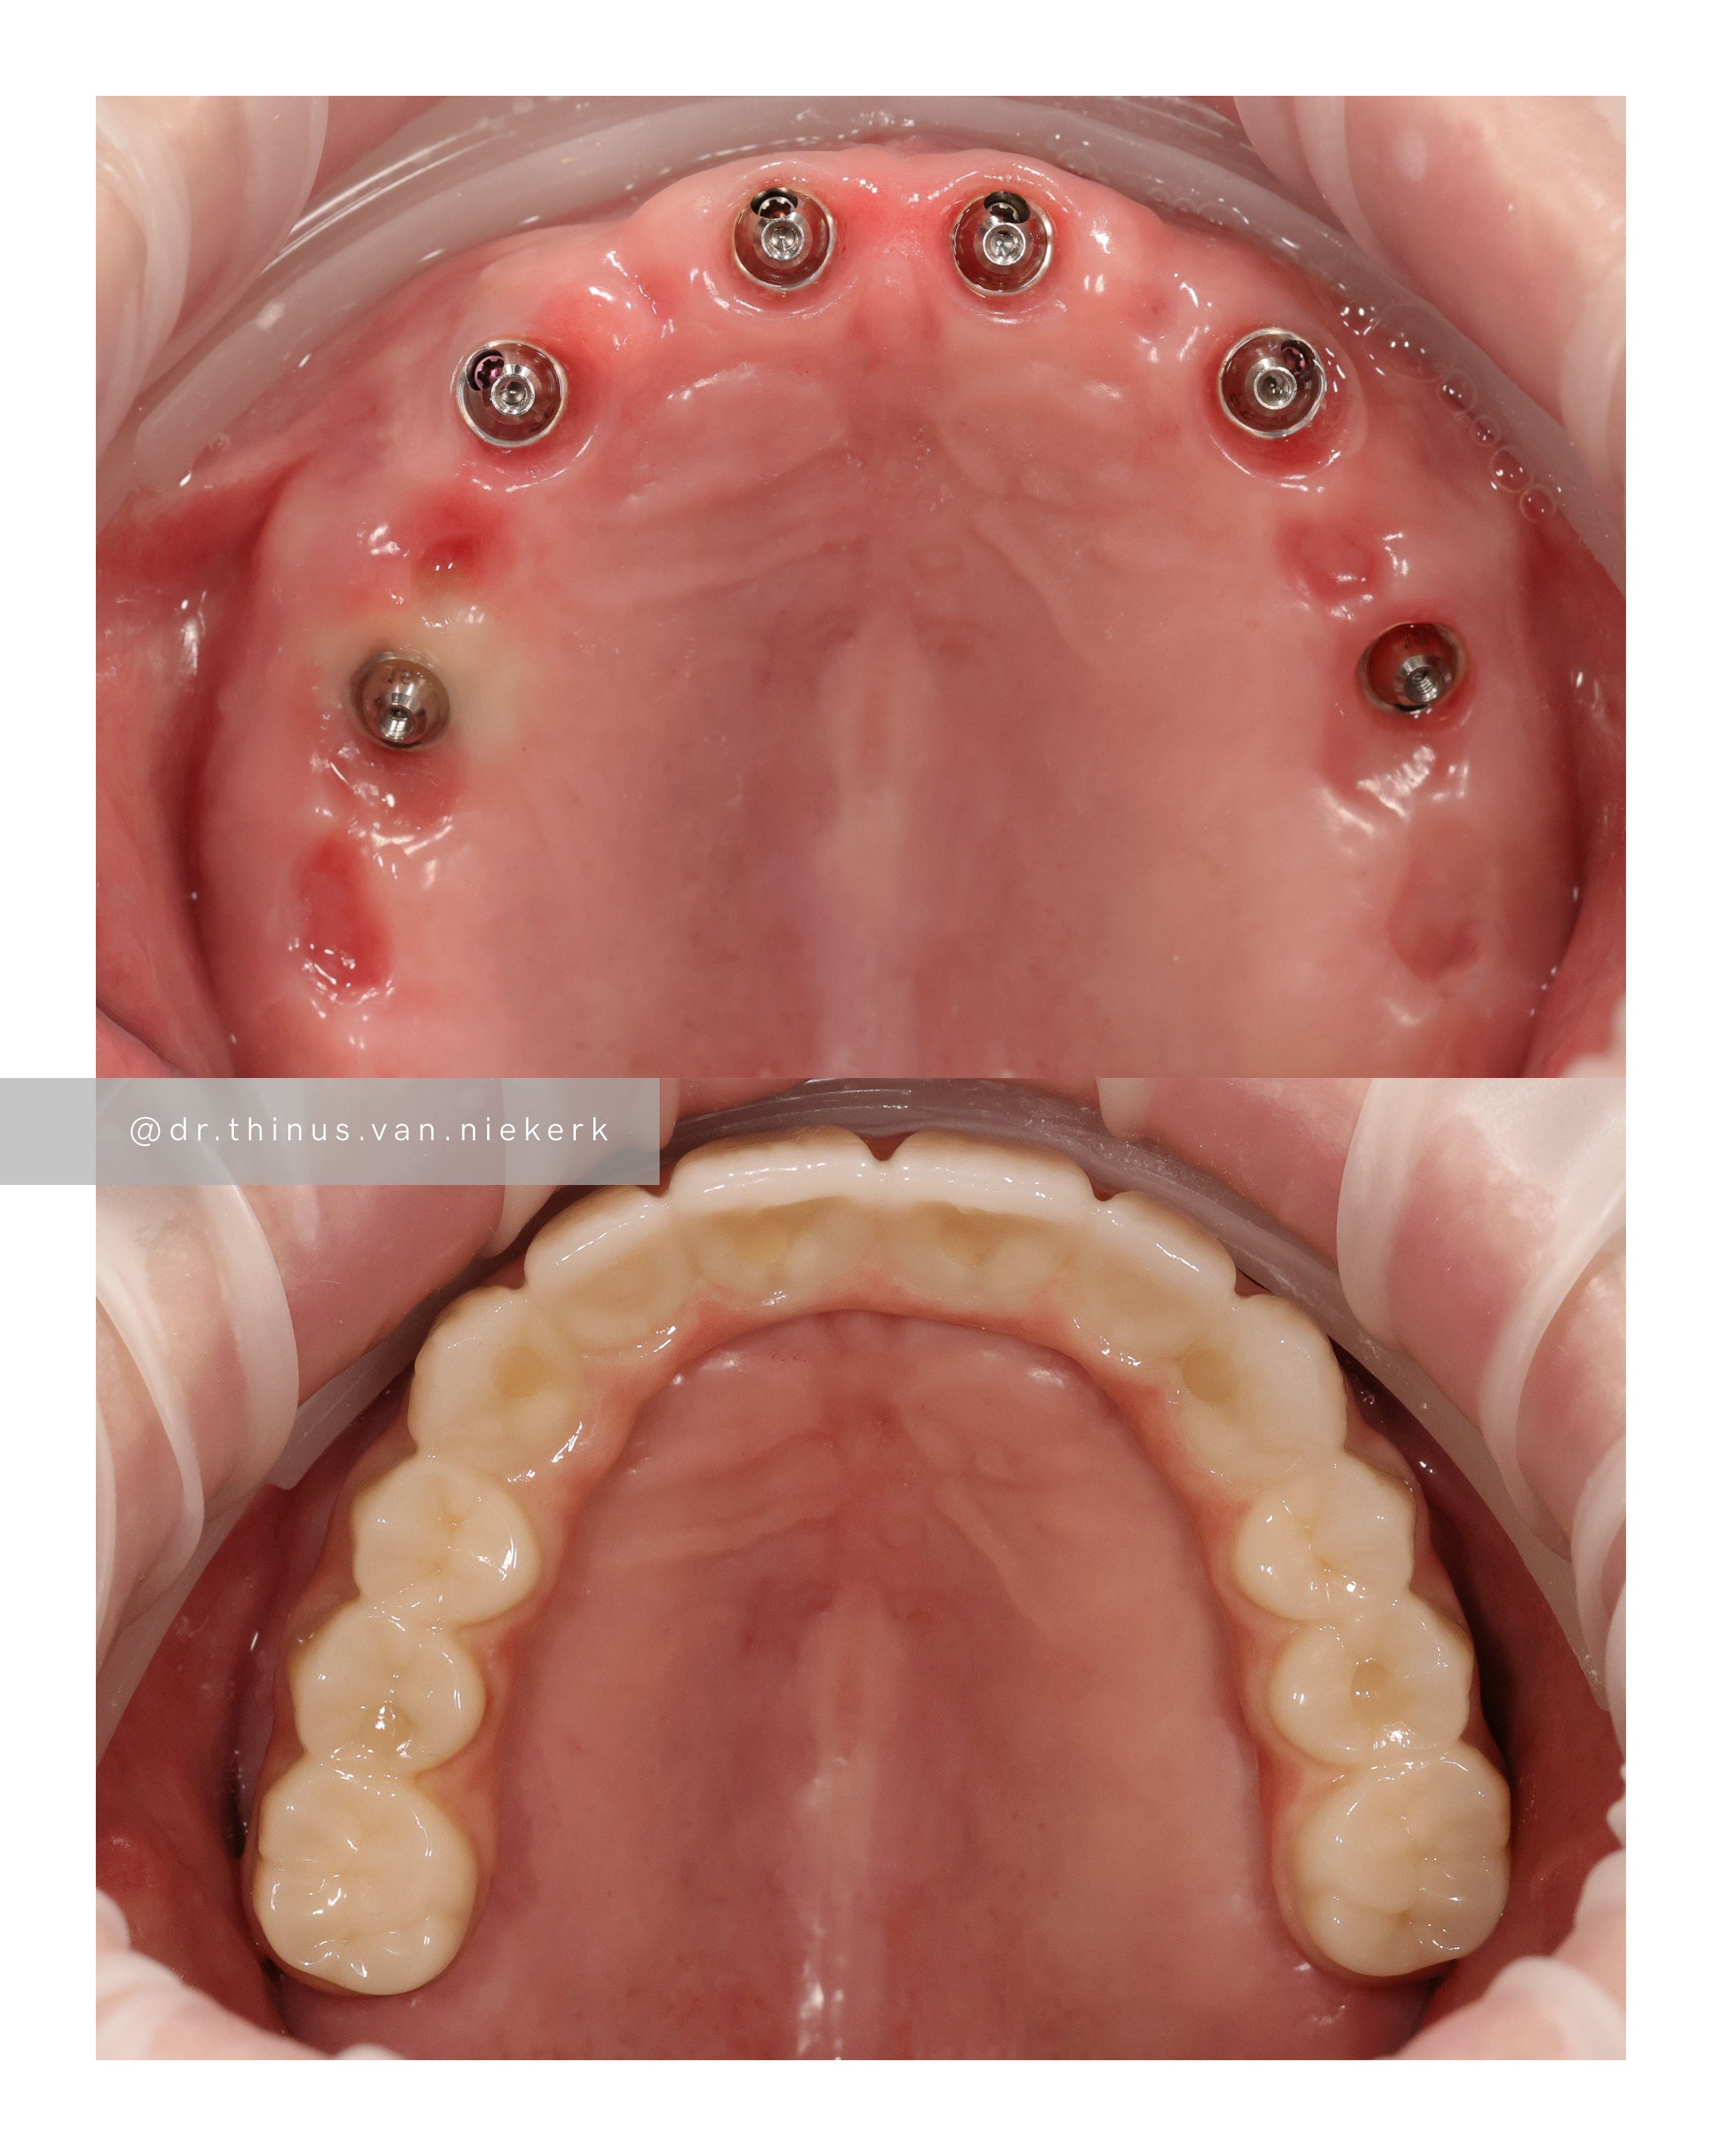

TREATMENT OBJECTIVE

Our patient endured a long history of oral disease and associated infections. Our aim was to remove all elements of infection and disease and to restore function as quickly as possible. Six fully-guided implants were placed and immediately restored with implant-supported prosthesis in both the upper and lower jaws respectively. These were then converted to final zirconia framework prosthesis as healing and tissue remodeling allowed. The complete timeline for a treatment such as this varies from 6-24 months.

COMMENTS

This was a landmark case for our clinic – being the first fully digitally-planned upper and lower rehabilitation. This case demonstrated the power and effectiveness of digital implant-surgery planning and CAD design software. No adjustments were needed at the placement of the final lower prosthesis.